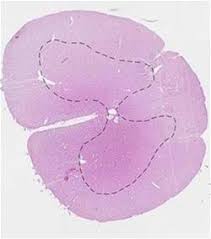

The central canal is continuous with the ventricular system of the brain. As part of the central nervous system, the spinal cord (medulla spinalis) is held in place by ligaments and is well protected in the spinal canal of the vertebral column. It starts at the foramen magnum as the. Clinical signs of spinal cord infarction include muscle weakness and paralysis with loss of reflexes. Spinal cord histology (transverse section): Gray matter (derived from embryonic mantle layer) is. Farlex partner medical dictionary © farlex 2012. Spinal canal and spinal cord.

Central canal of spinal cord (canalis centralis medullae spinalis); The spinal cord is the long, tubular structure in vertebrates that consists of a bundle of nervous tissue and support cells, connects with the brain, and extends lengthwise down the spinal cavity within the vertebral column (spine); The vertebral body (back bone) forms the front and the lamina (bony cerebrospinal fluid flows from the fourth ventricle into the central canal of the spinal cord and the subarachnoid space surrounding the brain and spinal cord. It is situated inside the vertebral canal of the vertebral column. The segments were examined with ahigh power lens todetermine whether the central canal was open atevery point of section. Central canal (derived from embryonic neural cavity) is lined by ependymal cells & filled with cerebrospinal fluid. The most common causes of infarction are vertebral. The central channel ( central canal ) is situated in the center of the spinal cord canal which contains cerebrospinal fluid.

Together with the cerebral ventricles, and the subarachnoid space of the central channel forms a single common cavity, since all. Haverkamp peter winningham winnie c. The central canal lies below and is connected to the ventricular system of the brain, from which it receives cerebrospinal fluid, and shares the same ependymal lining. The core consists mainly of two posterior (dorsal) horns, which extend toward the posterolateral surfaces of the cord, and two thicker anterior (ventral) horns, which extend toward the. Spinal cord cross section central canal. Surrounding the spinal cord and projecting downward is a slim connecting filament where the spinal cord ends (filum terminale). Gray matter (derived from embryonic mantle layer) is. Many present with serious acute symptoms such as paresthesia, paralysis, and loss of sensation or bladder and bowel function. The spinal cord forms a nearly cylindrical column that is situated within the spinal canal of the vertebral column. The central canal spans the length of the spinal cord from the caudal angle of the fourth ventricle to the conus medullaris. Spinal cord infarction (also known as a spinal stroke) refers to the death of nervous tissue, which results from an interruption of the arterial supply. The most common causes of infarction are vertebral. Central nervous system spinal cord.